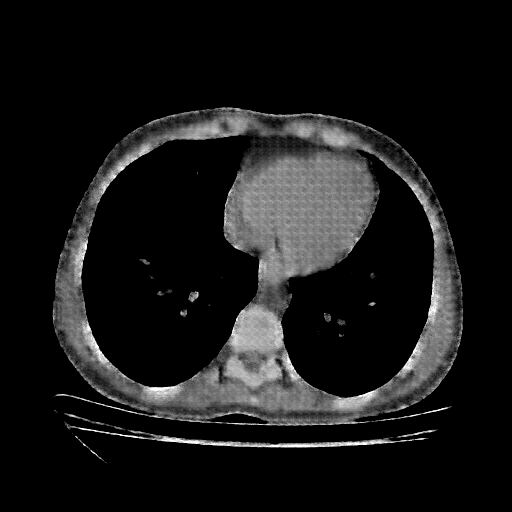

Generated VENOUS CT scan (A→B translation)

No window - Raw intensity values

Lung window (WL -600, WW 1500 β†’ Low βˆ’1350, High +150)

Mediastinum window (WL 40, WW 400 β†’ Low βˆ’160, High +240)